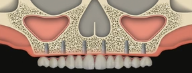

CLINICAL VIDEO All-on-4 Upper Jaw Implant Surgery - Surgical steps, Implant Plac

CAT# CV-052

All-on-4 Upper Jaw Implant Surgery - Surgical steps, Implant Placement, 3D treatment planning and immediate fixed hybrid prostheses delivery (Part 2)

Dr. Sascha Jovanovic